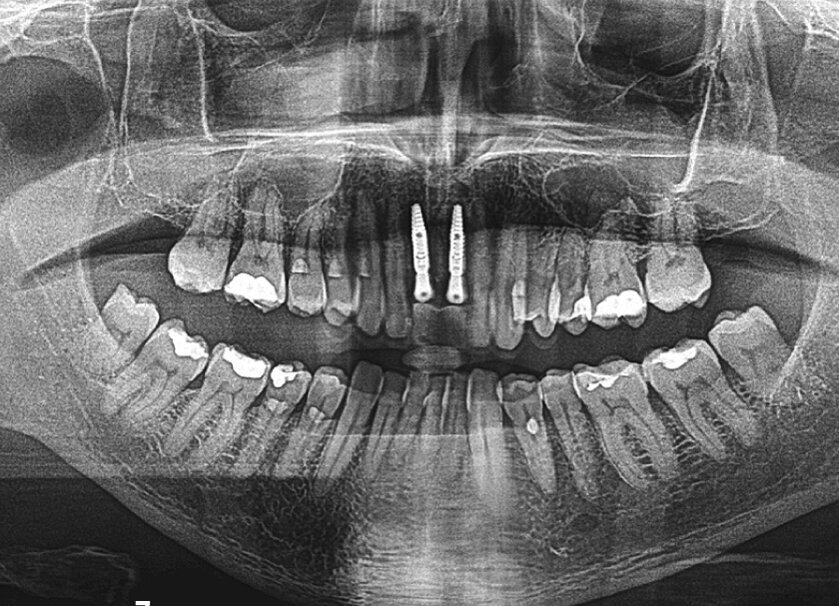

Budući da se to nije moglo isključiti za zub 21, u narednim posjetima provedeno je endodontsko liječenje s naknadnim punjenjem korijenskog kanala s MTA-om do pukotine (Slika 3.). Budući da je pacijent izrazio želju da se ne narušava estetika, za splintiranje je upotrijebljena palatinalna udlaga od PMMA-e (Slika 4.). Nakon tri mjeseca uočena je sve veća promjena boje zuba 21 i perzistentna pomičnost II. stupnja (Slika 5.). Nakon detaljnog informiranja o raznim mogućnostima liječenja kliničar i pacijent donijeli su odluku o implantoprotetskoj terapiji. CBCT snimljen tijekom planiranja terapije (Slika 6.), pokazao je blizak odnos prema vestibularnoj koštanoj lameli (položaj korijena I. razreda)14. Da bi se stvorio stabilan profil mekog i tvrdog tkiva i pacijentu što prije osigurao dobar estetski rezultat, kliničar se odlučio na imedijatnu implantaciju uz primjenu socket shield tehnike.

Odmah nakon implantacije postavljen je laboratorijski izrađen privremeni nadomjestak koji je uz pomoć privremenih nadogradnji pričvršćen na implantate 12 i 22. Na postoperativno snimljenom ortopantomogramu uočava se pravilan položaj implantata (Slika 7.). Sljedećeg dana nakon implantacije pacijent je došao na kontrolni pregled. Rana je bila bez znakova upale i simptoma. Na Slici 8. vidi se stanje prvog dana postoperativno i vestibularni fragment zuba. Nakon dvanaest dana uspostavila se stabilna arhitektura sluznice s vestibularnom ljuskom (Slika 9.).

Slika 7. Postoperativni ortopantomogram: pravilan položaj implantata 11 i 21